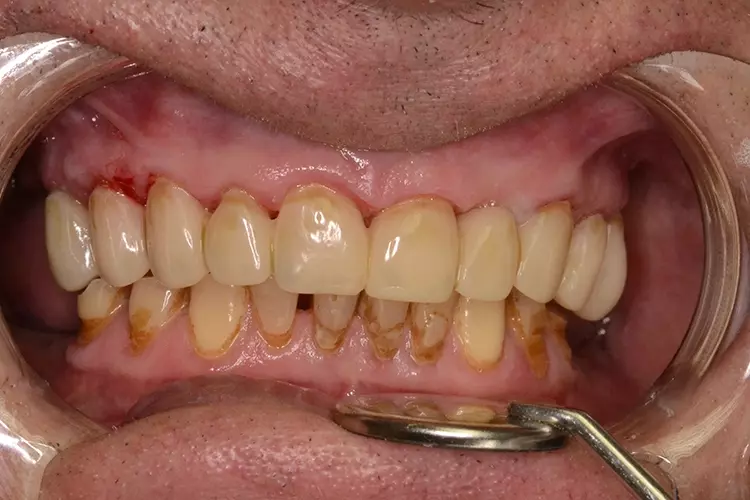

Neuversorgung Oberkieferfront auf Altimplantat 21

Die 49-jährige Patientin beklagte die ungleiche Höhe der Schneidekanten an den Kronen 11 und 21. In diesem Zusammenhang wurde das Gesamterscheinungsbild analysiert und entschieden, die Zähne 13-23 zu überkronen und dabei die Altkronen an 11 und an dem Implantat 21 zu erneuern. Die verschachtelt stehenden Zähne im Unterkiefer sollen im Nachgang per Aligner-Therapie ausgerichtet werden.

Dabei wurde die beabsichtigte Situation im Vorab per Wax-up simuliert. Beim Entfernen der Altkrone 21 wurde ersichtlich, dass ein Titanabutment eingesetzt wurde, an dem sich Konkremente und Zementreste befanden, die zu einer marginalen Mukositis am Implantat führten.